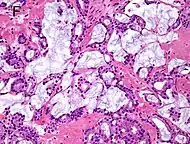

| Small-cell carcinoma | 0.3–2%[14][15][notes 1] | ![]() |

Half of cases have usual acinar components[1] |